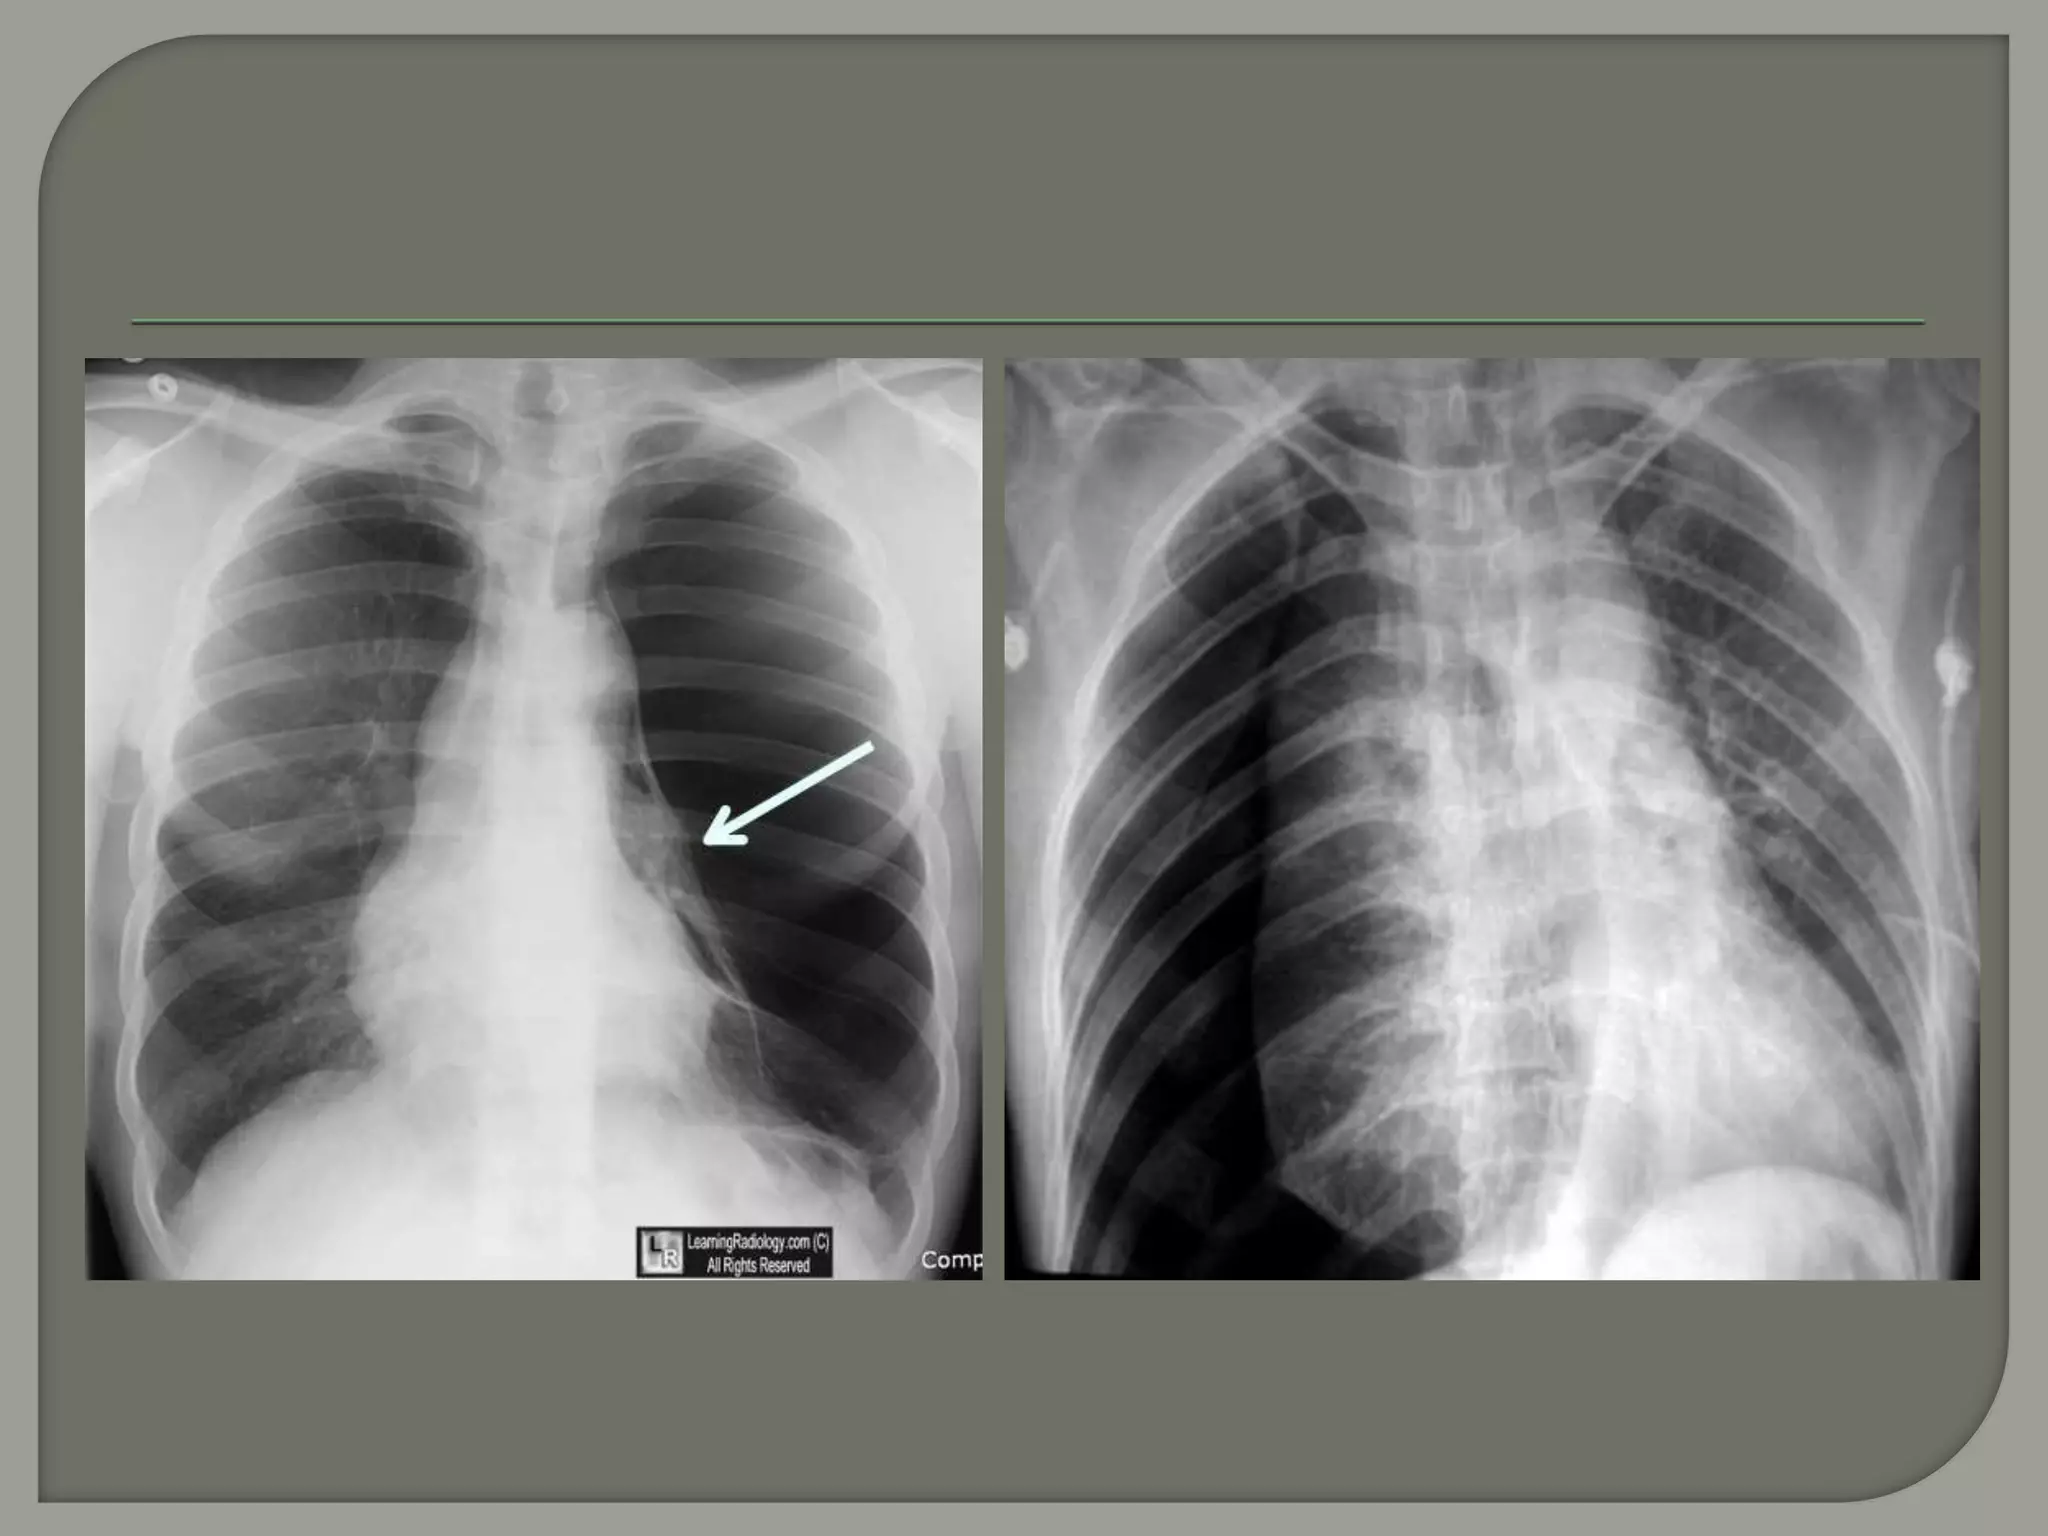

PA view showing

fully developed

Pneumatocele in

both lung. (black

arrow)

A. Frontal radiograph shows a thin-walled cavity (pneumatocele) in the left lung. B.

CT shows bilateral pneumatoceles and associated ground glass opacities. The

combination is suspicious for Pneumocystis carinii pneumonia

Trends Journal of Sciences Research, Volume 3, Issue 3, 2018, Pages 116–119.

https://doi.org/10.31586/Surgery.0303.02